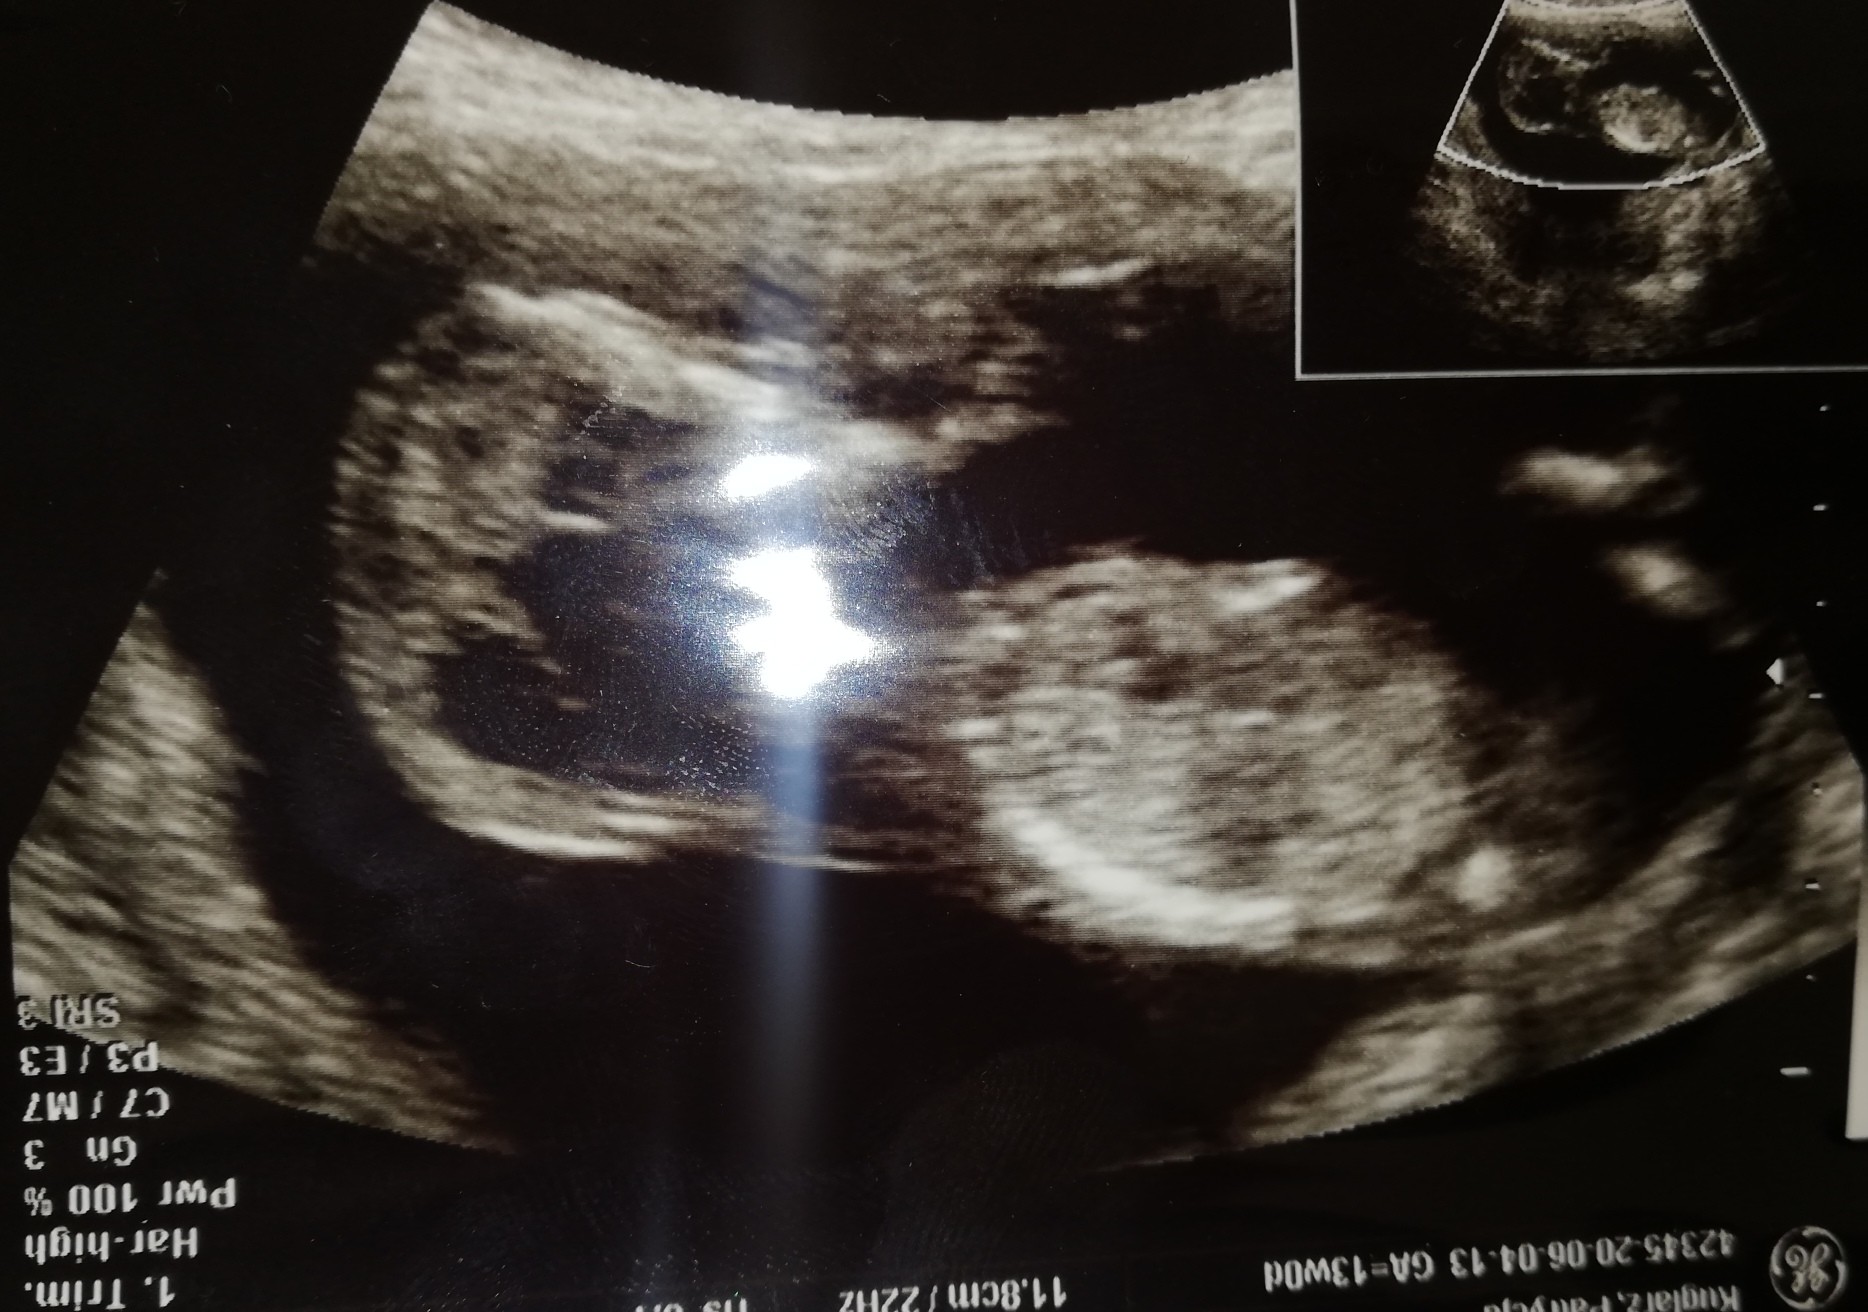

Hejka! Ja po prenatalnychNie udało się zmierzyć kości nosowej, bo bobas się strasznie kręcił, ale poza tym wszystkie inne parametry ok, a ryzyko niskie

Za tydzień zostanie uzupełnione to wynikami z krwi. No i prawdopodobnie chłopak